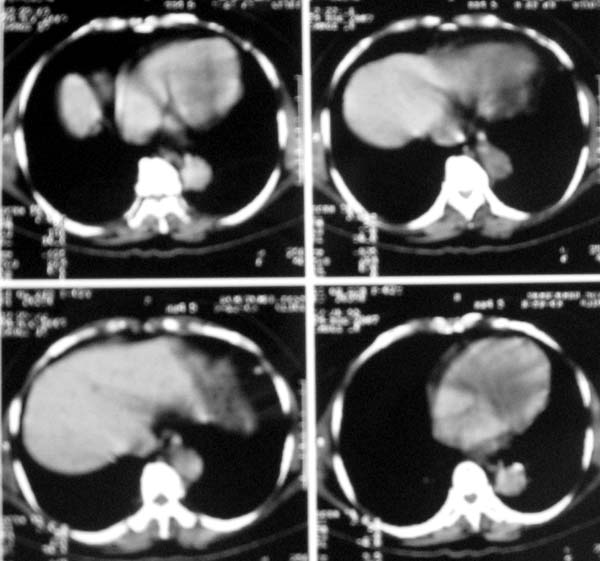

以下是引用zjzjr在2007-8-30 22:22:00的发言:[br]右上肺肺囊肿合并感染.右下肺肺大泡.左肺舌段感染.